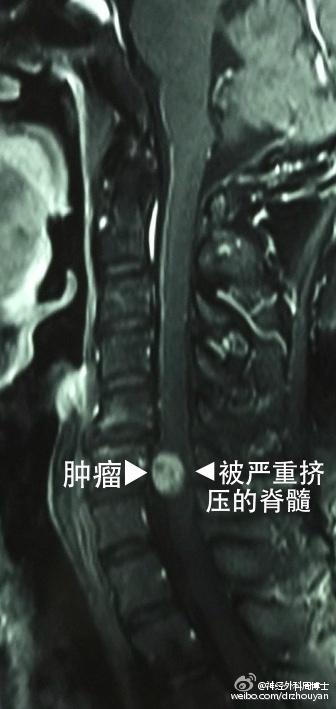

46岁的男性病人,这次来空军总医院的目的,原是慕名中医正骨科准备做手法推拿正骨治疗,可是经过细心的检查发现,颈椎6-7椎管内有一个肿瘤。

从去年10月份开始他感觉双腿麻木,尤其是左腿,一直以为是腰椎间盘突出,也一直做着腰椎的理疗、按摩、睡硬板床,可是没有任何好转,并且麻木感从腿开始逐渐向上发展。今年4月份,胸部开始有束缚感,就如同皮带紧紧地捆着胸廓,喘不上气。而且,左腿也开始活动不利索,排泄大小便也越来越费劲。